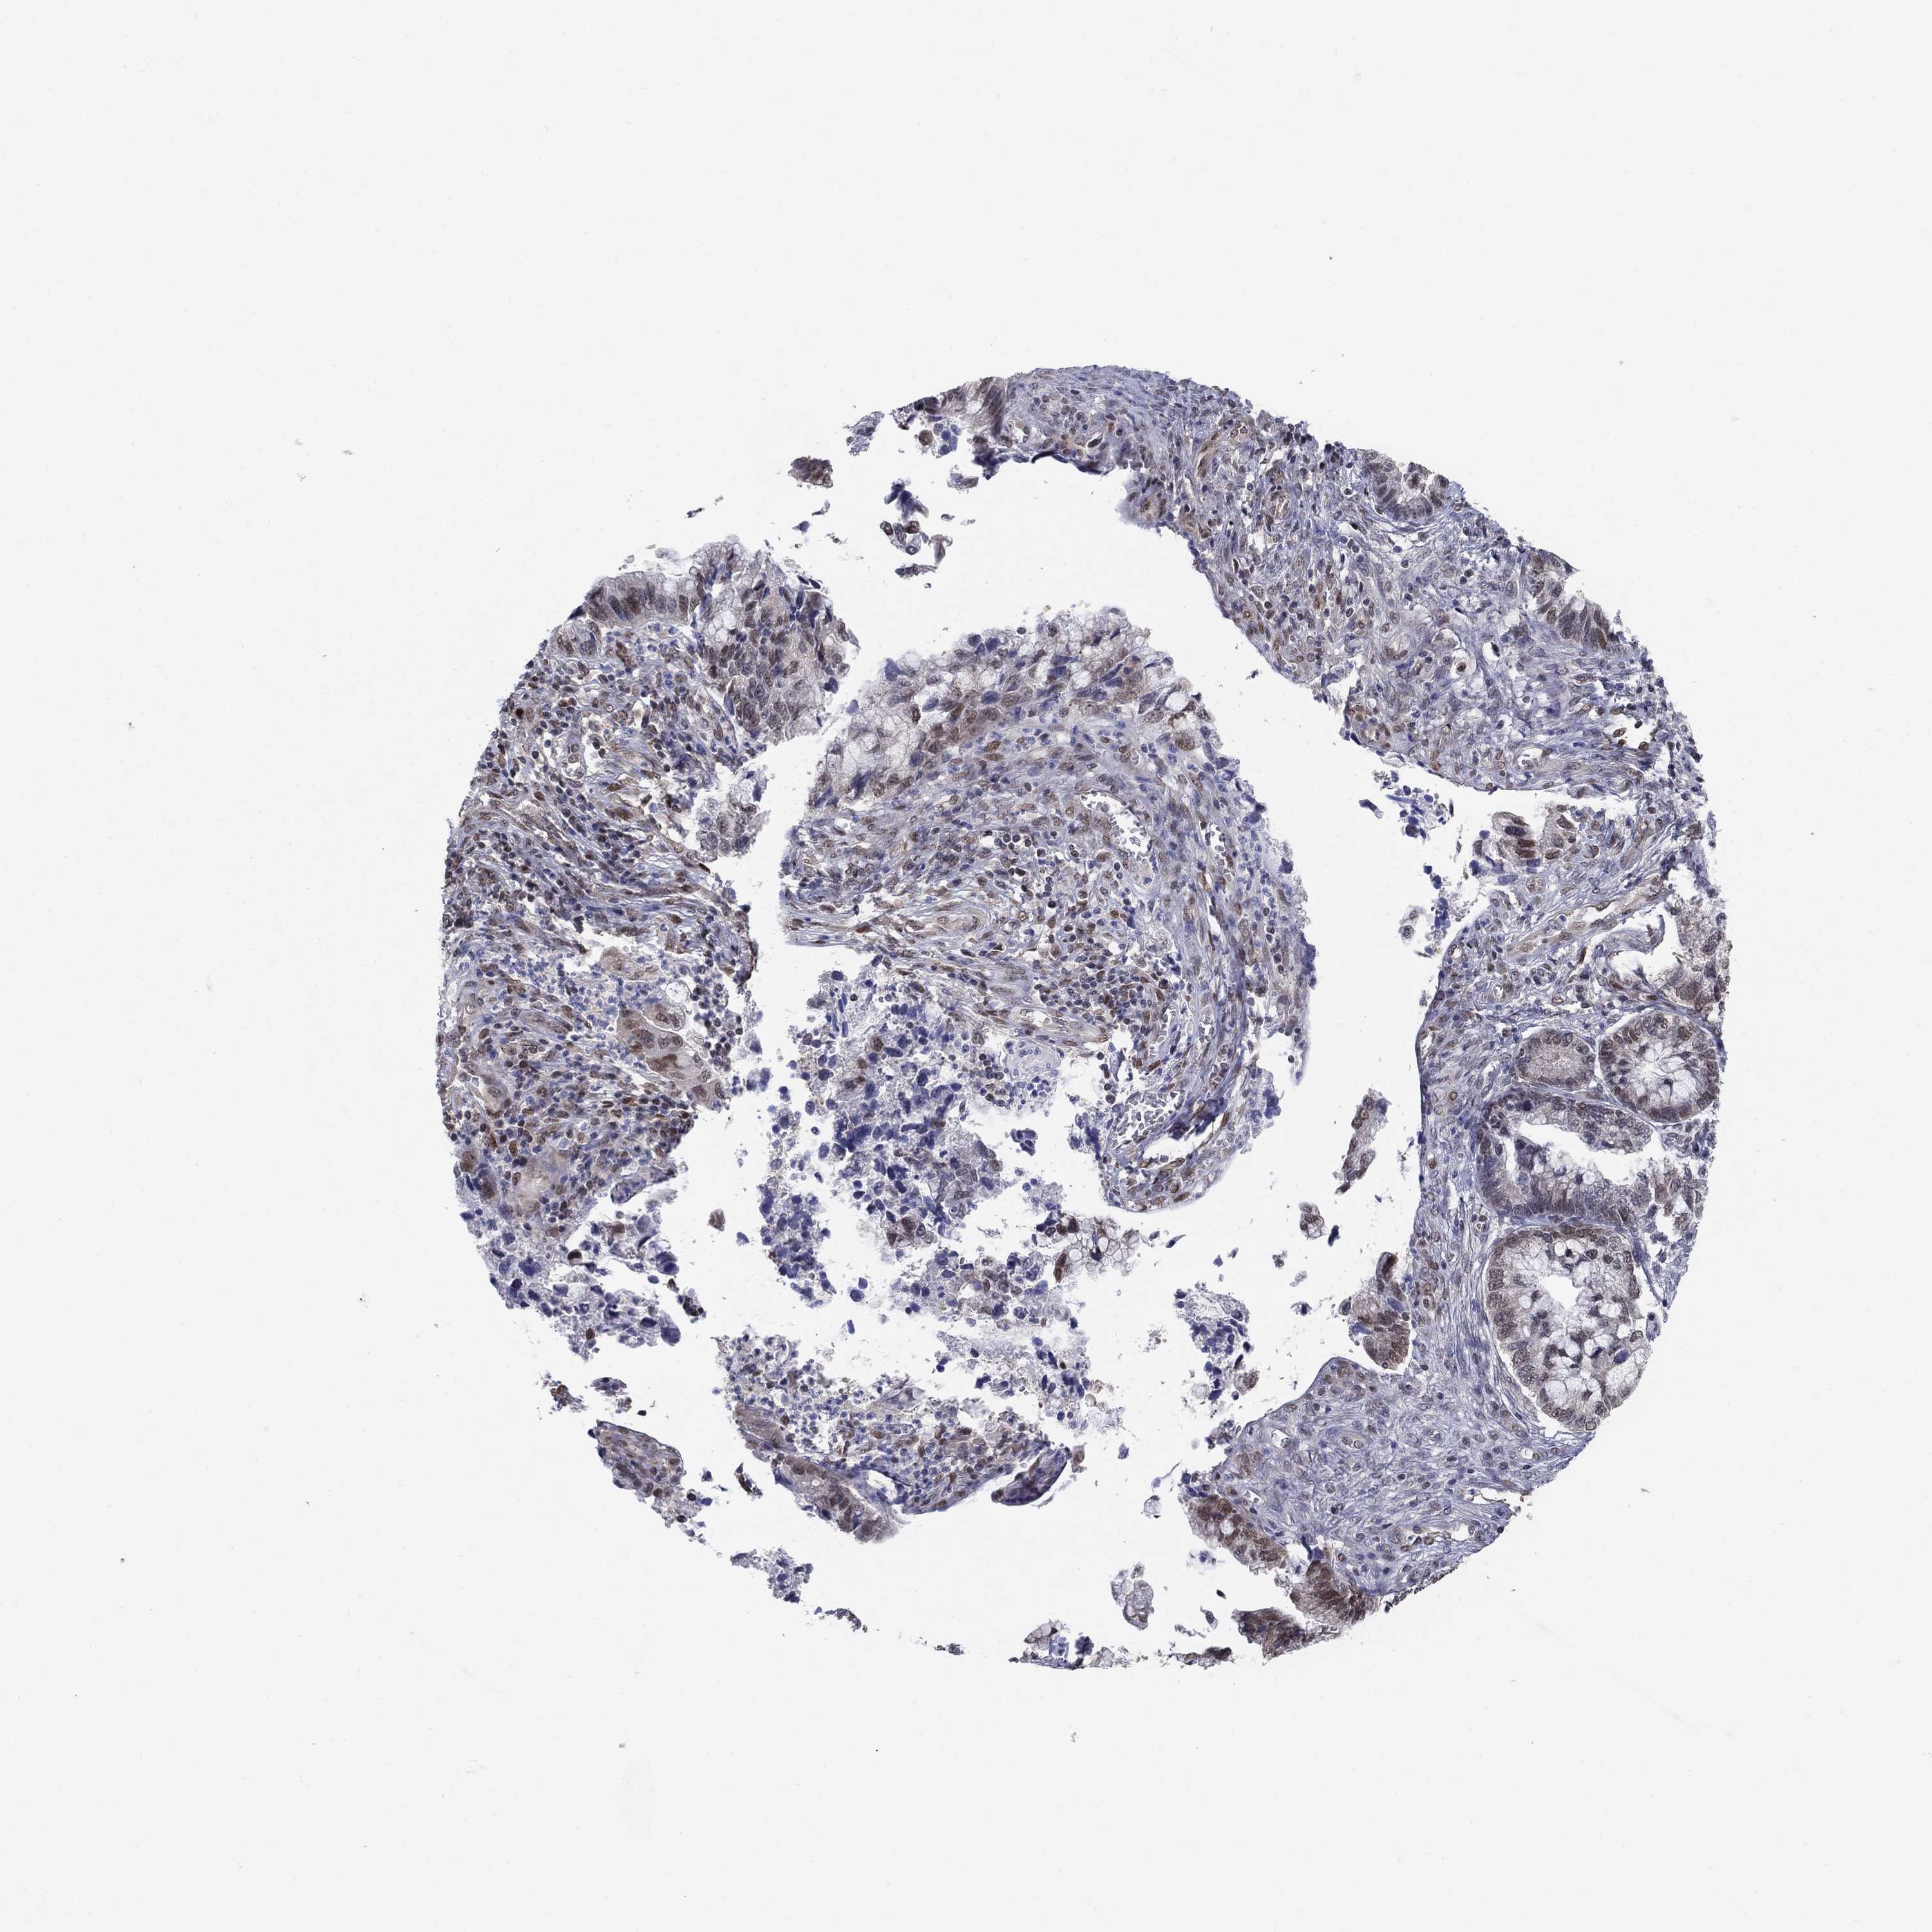

CERVICAL CANCER - Protein expressioni

A mouse-over function shows sample information and annotation data. Click on an image to view it in a full screen mode. Samples can be filtered based on level of antibody staining by selecting one or several of the following categories: high, medium, low and not detected. The assay and annotation is described here.

Note that samples used for immunohistochemistry by the Human Protein Atlas do not correspond to samples in the TCGA dataset.

Antibody stainingi

Antibody staining in the annotated cell types in the current human tissue is reported as not detected, low, medium, or high, based on conventional immunohistochemistry profiling in selected tissues. This score is based on the combination of the staining intensity and fraction of stained cells.

Each image is clickable and will lead to virtual microscopy that enables deeper exploration of all samples and also displays staining intensity scores, fraction scores and subcellular localization as well as patient and tissue information for each sample.

Antibody HPA042294

Staining

High

Medium

Low

Not detected

Intensity

Strong

Moderate

Weak

Negative

Quantity

>75%

75%-25%

<25%

None

Location

Nuclear

Cytoplasmic/membranous

Cytoplasmic/membranous,nuclear

Squamous cell carcinoma, NOS

Adenocarcinoma, NOS